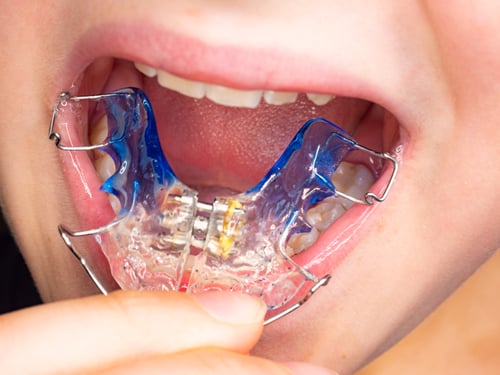

這是需要手動轉動螺絲的擴弓裝置。如果是固定在牙齒上的稱為 RPE (Rapid Palatal Expander),如果是活動可摘式的則統稱為活動式擴弓器。

- 運作原理: 透過裝置中央的螺旋開關,家長或患者定期旋轉螺絲產生機械力。它主要透過牙齒的位移帶動骨骼調整,雖然旨在將上顎骨的正中縫隙張開(骨骼擴張),但常伴隨牙齒移動變成假性擴弓(牙弓擴張)。

- 舒適度: 異物感較強,剛調整完會有明顯的腫脹感或發音不清楚。

- 優點: 擴張力強且穩定,對於骨骼發育尚未完全的青少年效果顯著。

- 缺點: 需高度配合轉螺絲,清潔較困難,若為活動式容易遺失。